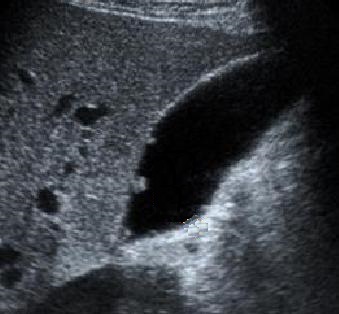

Image echographique d'une polyp

adenomateuse de type sessile supracentimetrique (

fleche rouge ) |